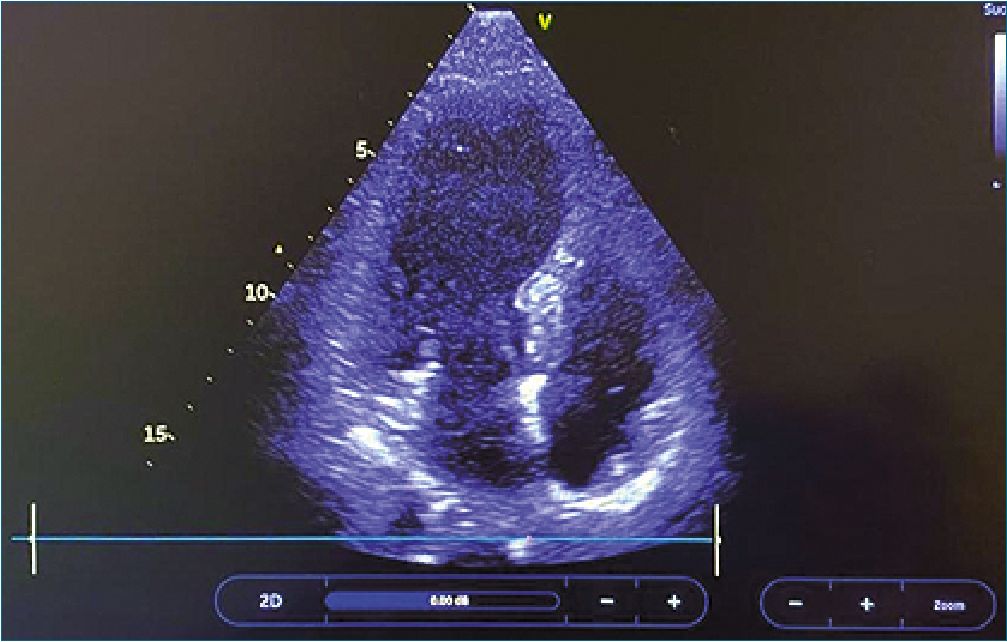

Como parte del estudio hemodinámico, se realizó ecocardiograma transtorácico POCUS, informado como ventrículo izquierdo no dilatado, con disquinesia, función sistólica global levemente deprimida y fracción de eyección de ventrículo izquierdo (FEVI) 47%. Luego de 6 h de reanimación, se realizó nuevo control ecocardiográfico (Figura 1) por cardiólogo de imágenes, que confirmó hipoquinesia del ventrículo izquierdo, dilatación apical y evidencia de disfunción diastólica. Se tomó electrocardiograma (ECG) (Figura 2) que evidenció supradesnivel del segmento ST anterolateral. Se solicitarón niveles séricos de troponina ultrasensible, que resultaron elevados,10 ng/ml (valor ref 0,01 ng/ml), por lo que se realizó estudio angiográfico coronario, que evidenció lecho vascular normal con flujo TIMI 3. Debido a la evolución clínica y a los hallazgos imagenológicos, se planteó en reunión multidisciplinaria, el diagnóstico de síndrome de Takotsubo (STT) asociado a anafilaxia.

Figura 1. Hipoquinesia y dilatación vértice del ventrículo izquierdo.